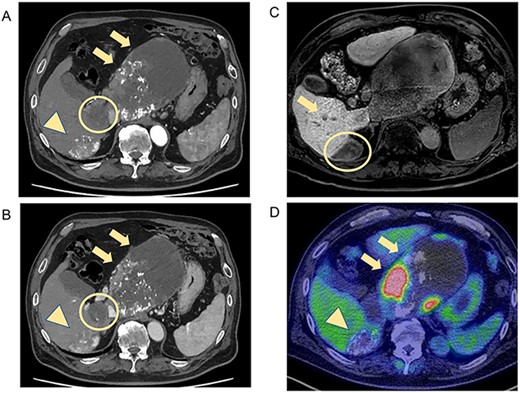

Histopathological findings showed extensive necrosis and hemorrhage of the tumors, probably because of LEN and TACE. One of the S1 tumors was a well to poorly differentiated HCC with a total size of 135 × 80 mm and viable lesion size of 39 × 31 mm (Fig. 3a). The other S1 HCC was a total size of 30 × 25 mm and a viable lesion size of 17 × 2 mm (Fig. 3b), and the S6/7 HCC was a total size of 65 × 40 mm and a viable lesion size of 15 × 2 mm (Fig. 3c). The nodule removed from the Morrison’s fossa was confirmed to be peritoneal dissemination. The noncancerous liver showed mild chronic inflammation in the portal areas with liver cirrhosis (A1, F4).

Photographs showing extensive necrosis and hemorrhage of the resected tumors after LEN and TACE. (A) One of the S1 tumors was a well to poorly differentiated HCC, of which 11% was viable tumor cells. (B) The other S1 tumor was a well to moderately differentiated HCC with 5% viable lesions. (C) The S6/7 tumor was a well to moderately differentiated HCC with 2% viable lesions. Scale bar = 10 mm. S, segment.